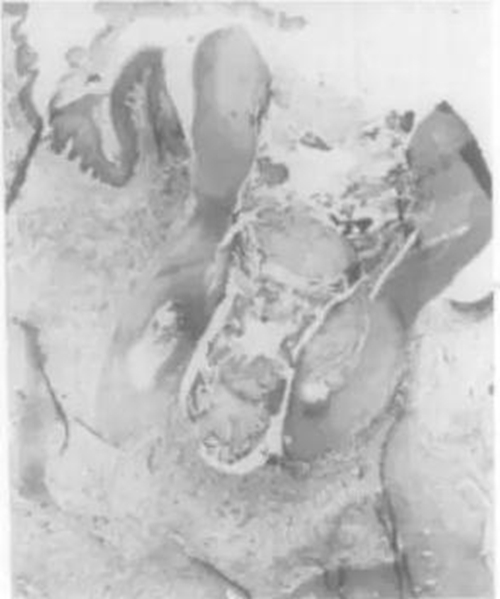

AB-膿腫;GR-肉芽腫;LU-空腔;EP-上皮;D-牙本質(zhì);RC-根管;a,b-膿腫;c,d-肉芽腫;b,d-病損有出現(xiàn)上皮化;e-真囊腫 (true cyst);f-袋性囊腫(pocket cyst)

病損上皮化(epithelialized lesion):Nair et al.(1996)已經(jīng)明確提出臨床超過50%的根尖肉芽腫都能檢查出上皮的存在。當上皮細胞開始受刺激增殖時,它能沿任何方向以隨機的方式組成不規(guī)則的上皮團塊,有時甚至能生長至根管內(nèi),于根尖孔形成塞狀封閉(Nair & Schroeder 1985),所以單單上皮組織的存在并不是囊腫的診斷標準。

發(fā)生率:雖然不同的研究報道的范圍是6-55%(Bhaskar 1966; Lalonde & Luebke 1968; Nair et al. 1996; Simon 1980),但是現(xiàn)在我們知道了實際上超過50%的病例只是發(fā)生上皮化的病損。囊腫的診斷應該依據(jù)嚴格的組織病理學標準,那就是在連續(xù)的切片上觀察到完整的上皮包裹。所以真正的根尖周囊腫所占的比例僅為15% ,這其中又細分為袋性囊腫和真囊腫(Nair et al. 1996)。

袋性囊腫(Pocket cyst):病損被上皮完整包裹,成盲袋狀開口于根尖孔與根管系統(tǒng)相通,發(fā)生率為6%(Nair et al. 1996)。關(guān)于其形成機制,學者推測病變早期是為了對抗根尖1/3細菌的刺激而在根尖孔處積聚形成中性粒細胞墻。之后由于細胞的死亡和降解逐漸形成空腔和囊壁,而出現(xiàn)的細胞濃度梯度趨化更多的中性粒細胞聚集,使囊腔逐漸擴大,最終成為與根管相連的囊性病變(Simon 1980)。

真囊腫(True cyst):完全獨立于根管系統(tǒng)且有完整上皮包膜的病損,發(fā)生率為9%(Nair et al. 1996)。